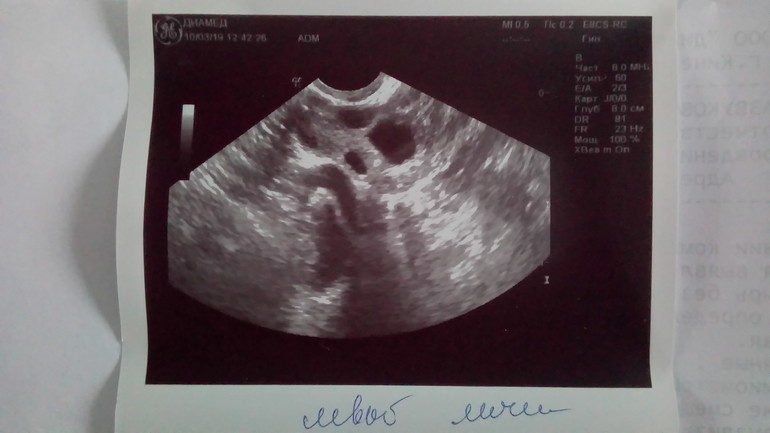

10.03.19г - На 8 день цикла УЗИ:

Эндометрий 9 мм

В ПЯ Фолликул 14*12 мм, остальные мелкие фолликулы 5 мм, 5 мм, 4 мм

В ЛЯ Фолликулы 11,5 мм, 6 мм, 6 мм, 5 мм.